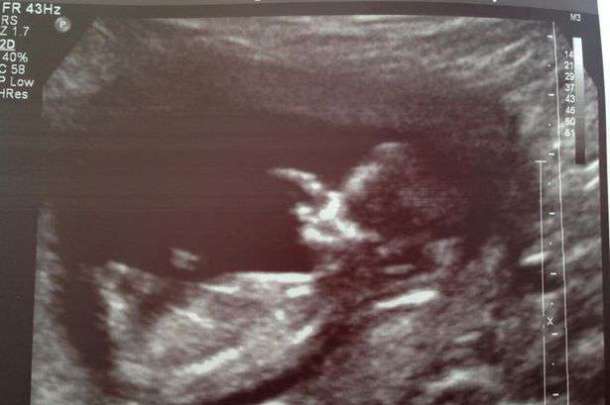

Dévastée par la perte de son petit-ami, Lizzy devait tout de même se rendre à l’hôpital afin d’effectuer quelques tests de suivi. Deux jours après le drame, elle apprend une nouvelle qui allait changer sa vie : elle est enceinte ! La jeune femme a attendu que les funérailles de Grant soient passées avant d’annoncer la nouvelle à la famille de son défunt fiancé.